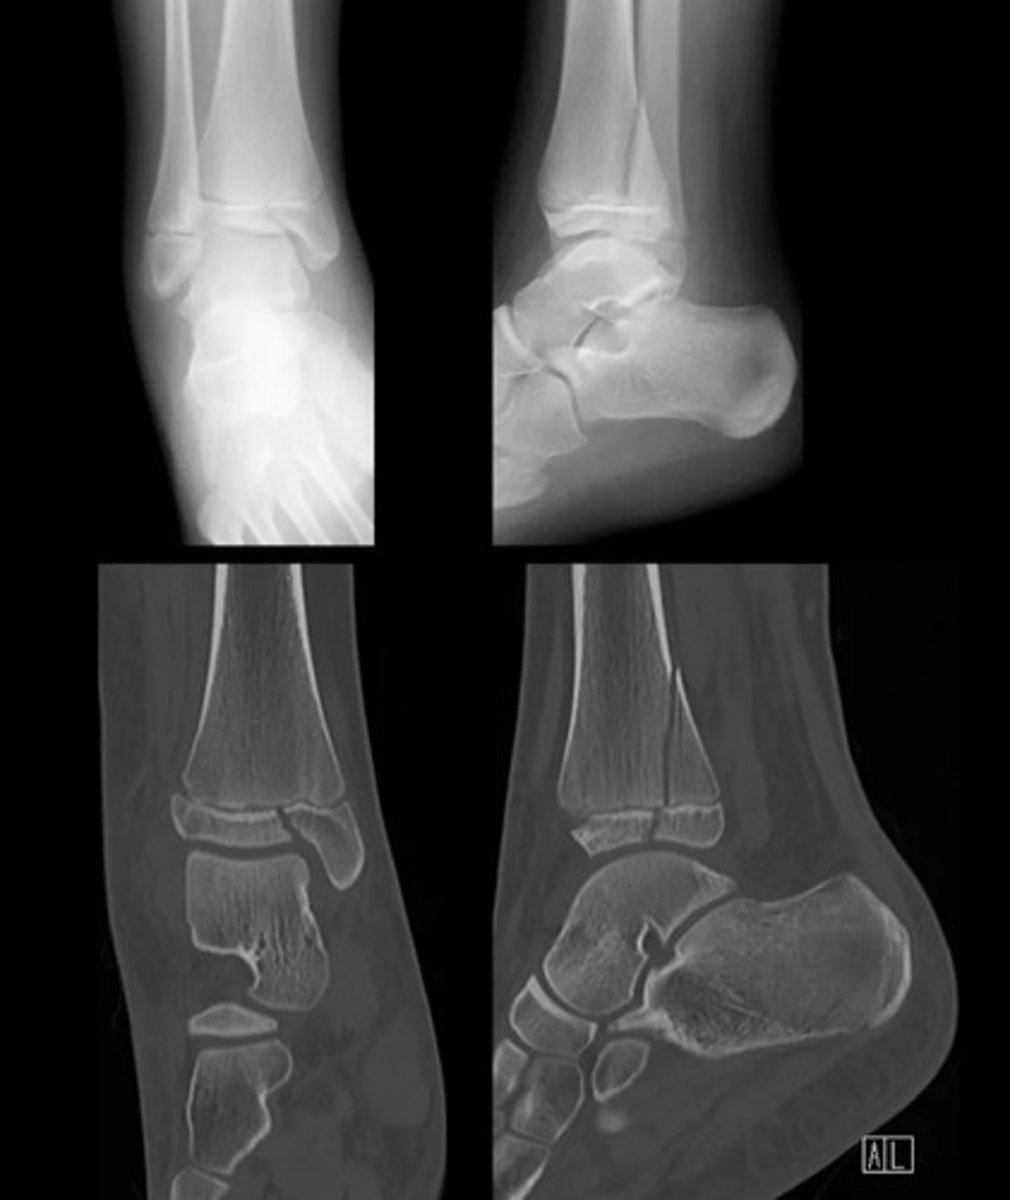

There are complete fractures involving the distal third diaphyses of both the tibia and fibula. The tibial fracture is oblique. The distal tibial fragment is laterally displaced and angulated relative to the proximal shaft. The fibula demonstrates an associated oblique fracture with mild displacement.

Weber A fracture of the fibula/ lateral malleolus

Weber B feature of the fibula/ lateral malleolus

Bimalleolar fracture.

Weber C

There is a transverse medial malleolus fracture

The distal tibiofibular joint is also widened